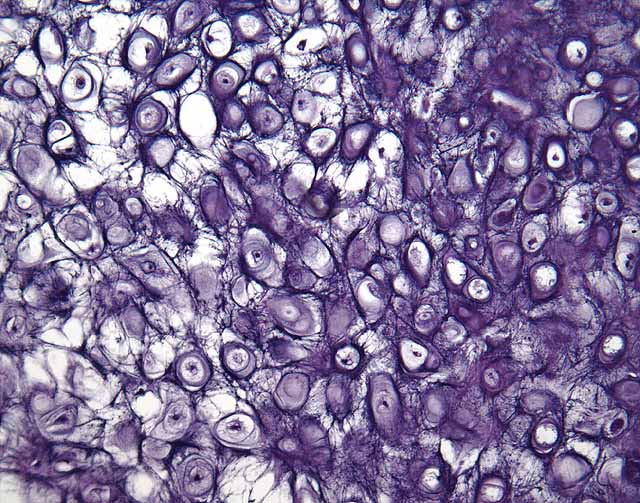

<p></p>

Transitional Epithelium